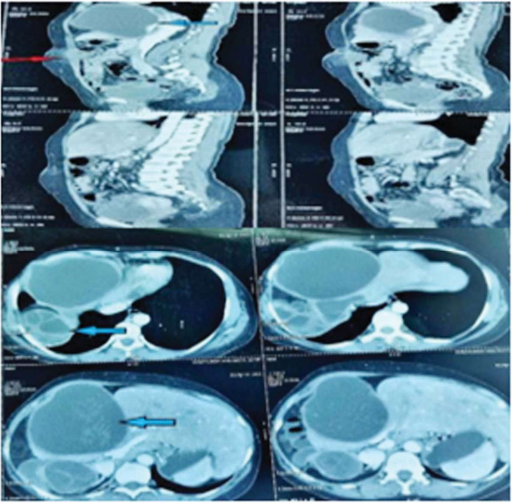

Port site hydatid cyst (Red arrow), liver hydatid cyst (blue arrow).

Description: No description available.

Intra-operative port site hydatid cyst.